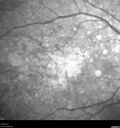

79 year old vision is in for a checkup with no visual complaints in the left eye. This is her better eye. VA 20/200 OD, 20/50 OS. 3 years ago she had a CRVO in the left eye. She is also diabetic for 20 years, has carotid insufficiency and anemia. Left eye shows CME. This was not treated and the vision improved to 20/40 over the next year although mild edema persisted.